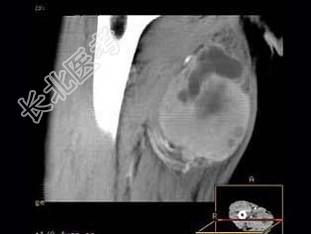

- 单项选择题男,30岁, 主诉右大腿肿块年余,逐渐增大, 局部胀痛及压痛,根据图像表现, 最可能的诊断是 ( )

D、横纹肌肉瘤